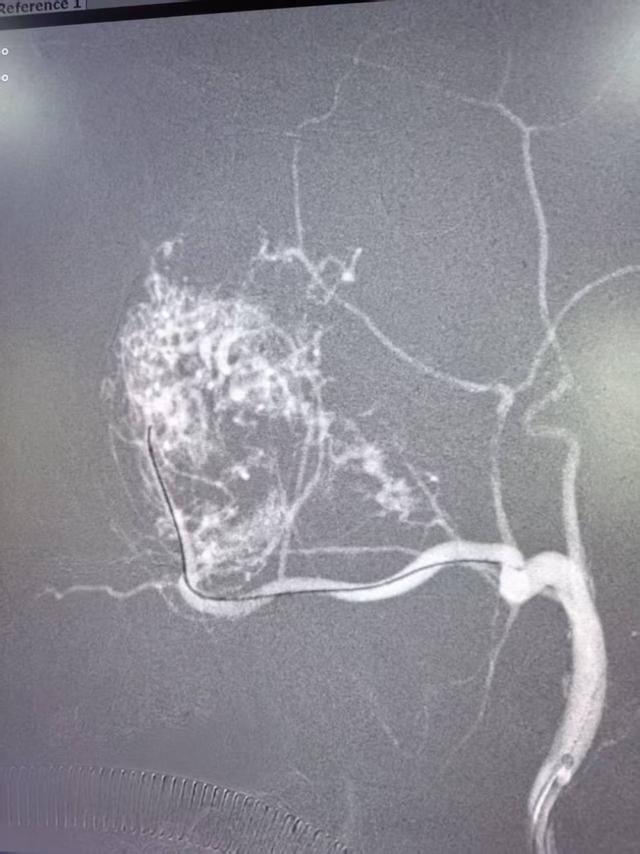

第一步:由刘超博副院长主刀,实施介入动脉栓塞术,堵塞肿瘤供血血管;

在白磊院长协调下,刘超博副院长凭借精湛技术成功栓塞责任血管(上颌内动脉),为后续手术奠定基础。得知患者家庭贫困,刘副院长特意叮嘱团队减轻其经济负担。

王松主任远赴乌鲁木齐联系设备厂家(美敦力),厂家了解情况后同意免费提供设备,以“试用”方式解决难题。经过4小时精密协作,团队成功完整切除血管瘤,术中输血1400毫升,过程平稳有序。